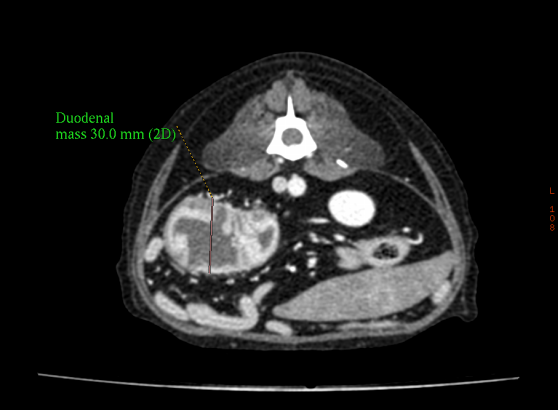

CT 촬영

단시간의 촬용으로 정밀한 3D입체영상을 얻을 수 있습니다.

• 장종양

만성구토 장종양

만성적인 구토의 원인이었던 장종양,

수술적 치료부터 항암 치료까지